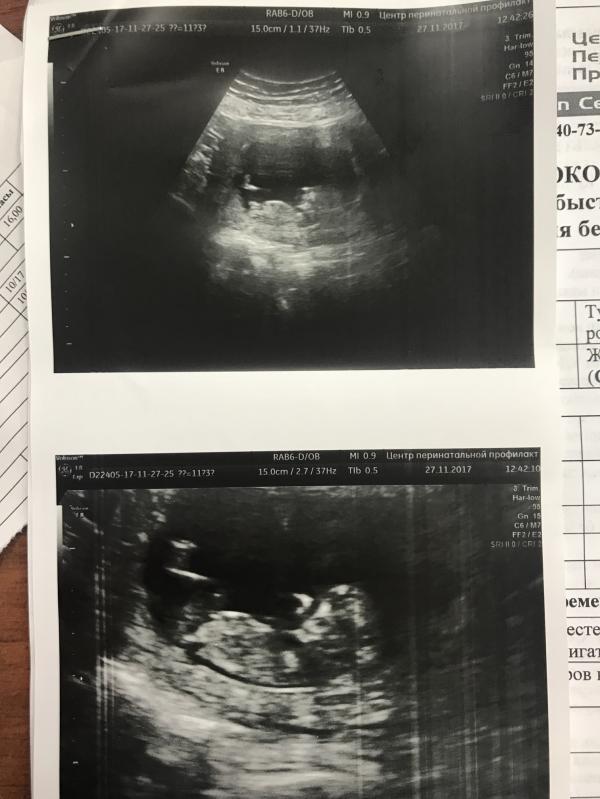

Сходила на УЗИ к Талько. 12 недель. Ребёнок здоров. Сказала похож на девочку. Я так расстроилась 😭😭😭